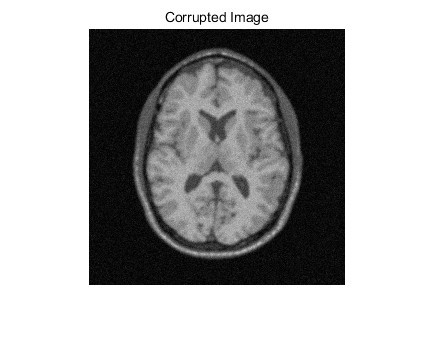

在图像处理领域,图像分割一直是一个关键的研究方向。今天咱们就来聊聊在 MATLAB 环境下,基于隐马尔可夫模型 - 高斯混合模型 - 期望最大化的图像分割算法,这个算法可是相当厉害,能有效将图像中的不同部分区分开来。

整体算法就是结合了 GMM、EM 和 MRF 来进行图像分割。首先用 GMM 对图像像素值进行建模,然后通过 EM 算法来优化 GMM 的参数,在这个过程中,借助 MRF 模型把像素间的空间关系考虑进去,从而得到更准确的分割结果。